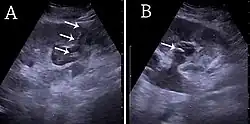

![]() (A) Ecografía renal del tubo de nefrostomía percutánea colocado a través de un cáliz en el polo inferior de un riñón con hidronefrosis. (B) El catéter de coleta se coloca en el cáliz dilatado. El tubo en (A) y la coleta en (B) están marcados con flechas blancas.[1] | ||

- ↑ Contenido copiado inicialmente de: Hansen, Kristoffer; Nielsen, Michael; Ewertsen, Caroline (2015). «Ultrasonografía del riñón: A Pictorial Review». Diagnostics 6 (1): 2. ISSN 2075-4418. PMC 4808817. PMID 26838799. doi:10.3390/diagnostics6010002. (CC-BY 4.0)